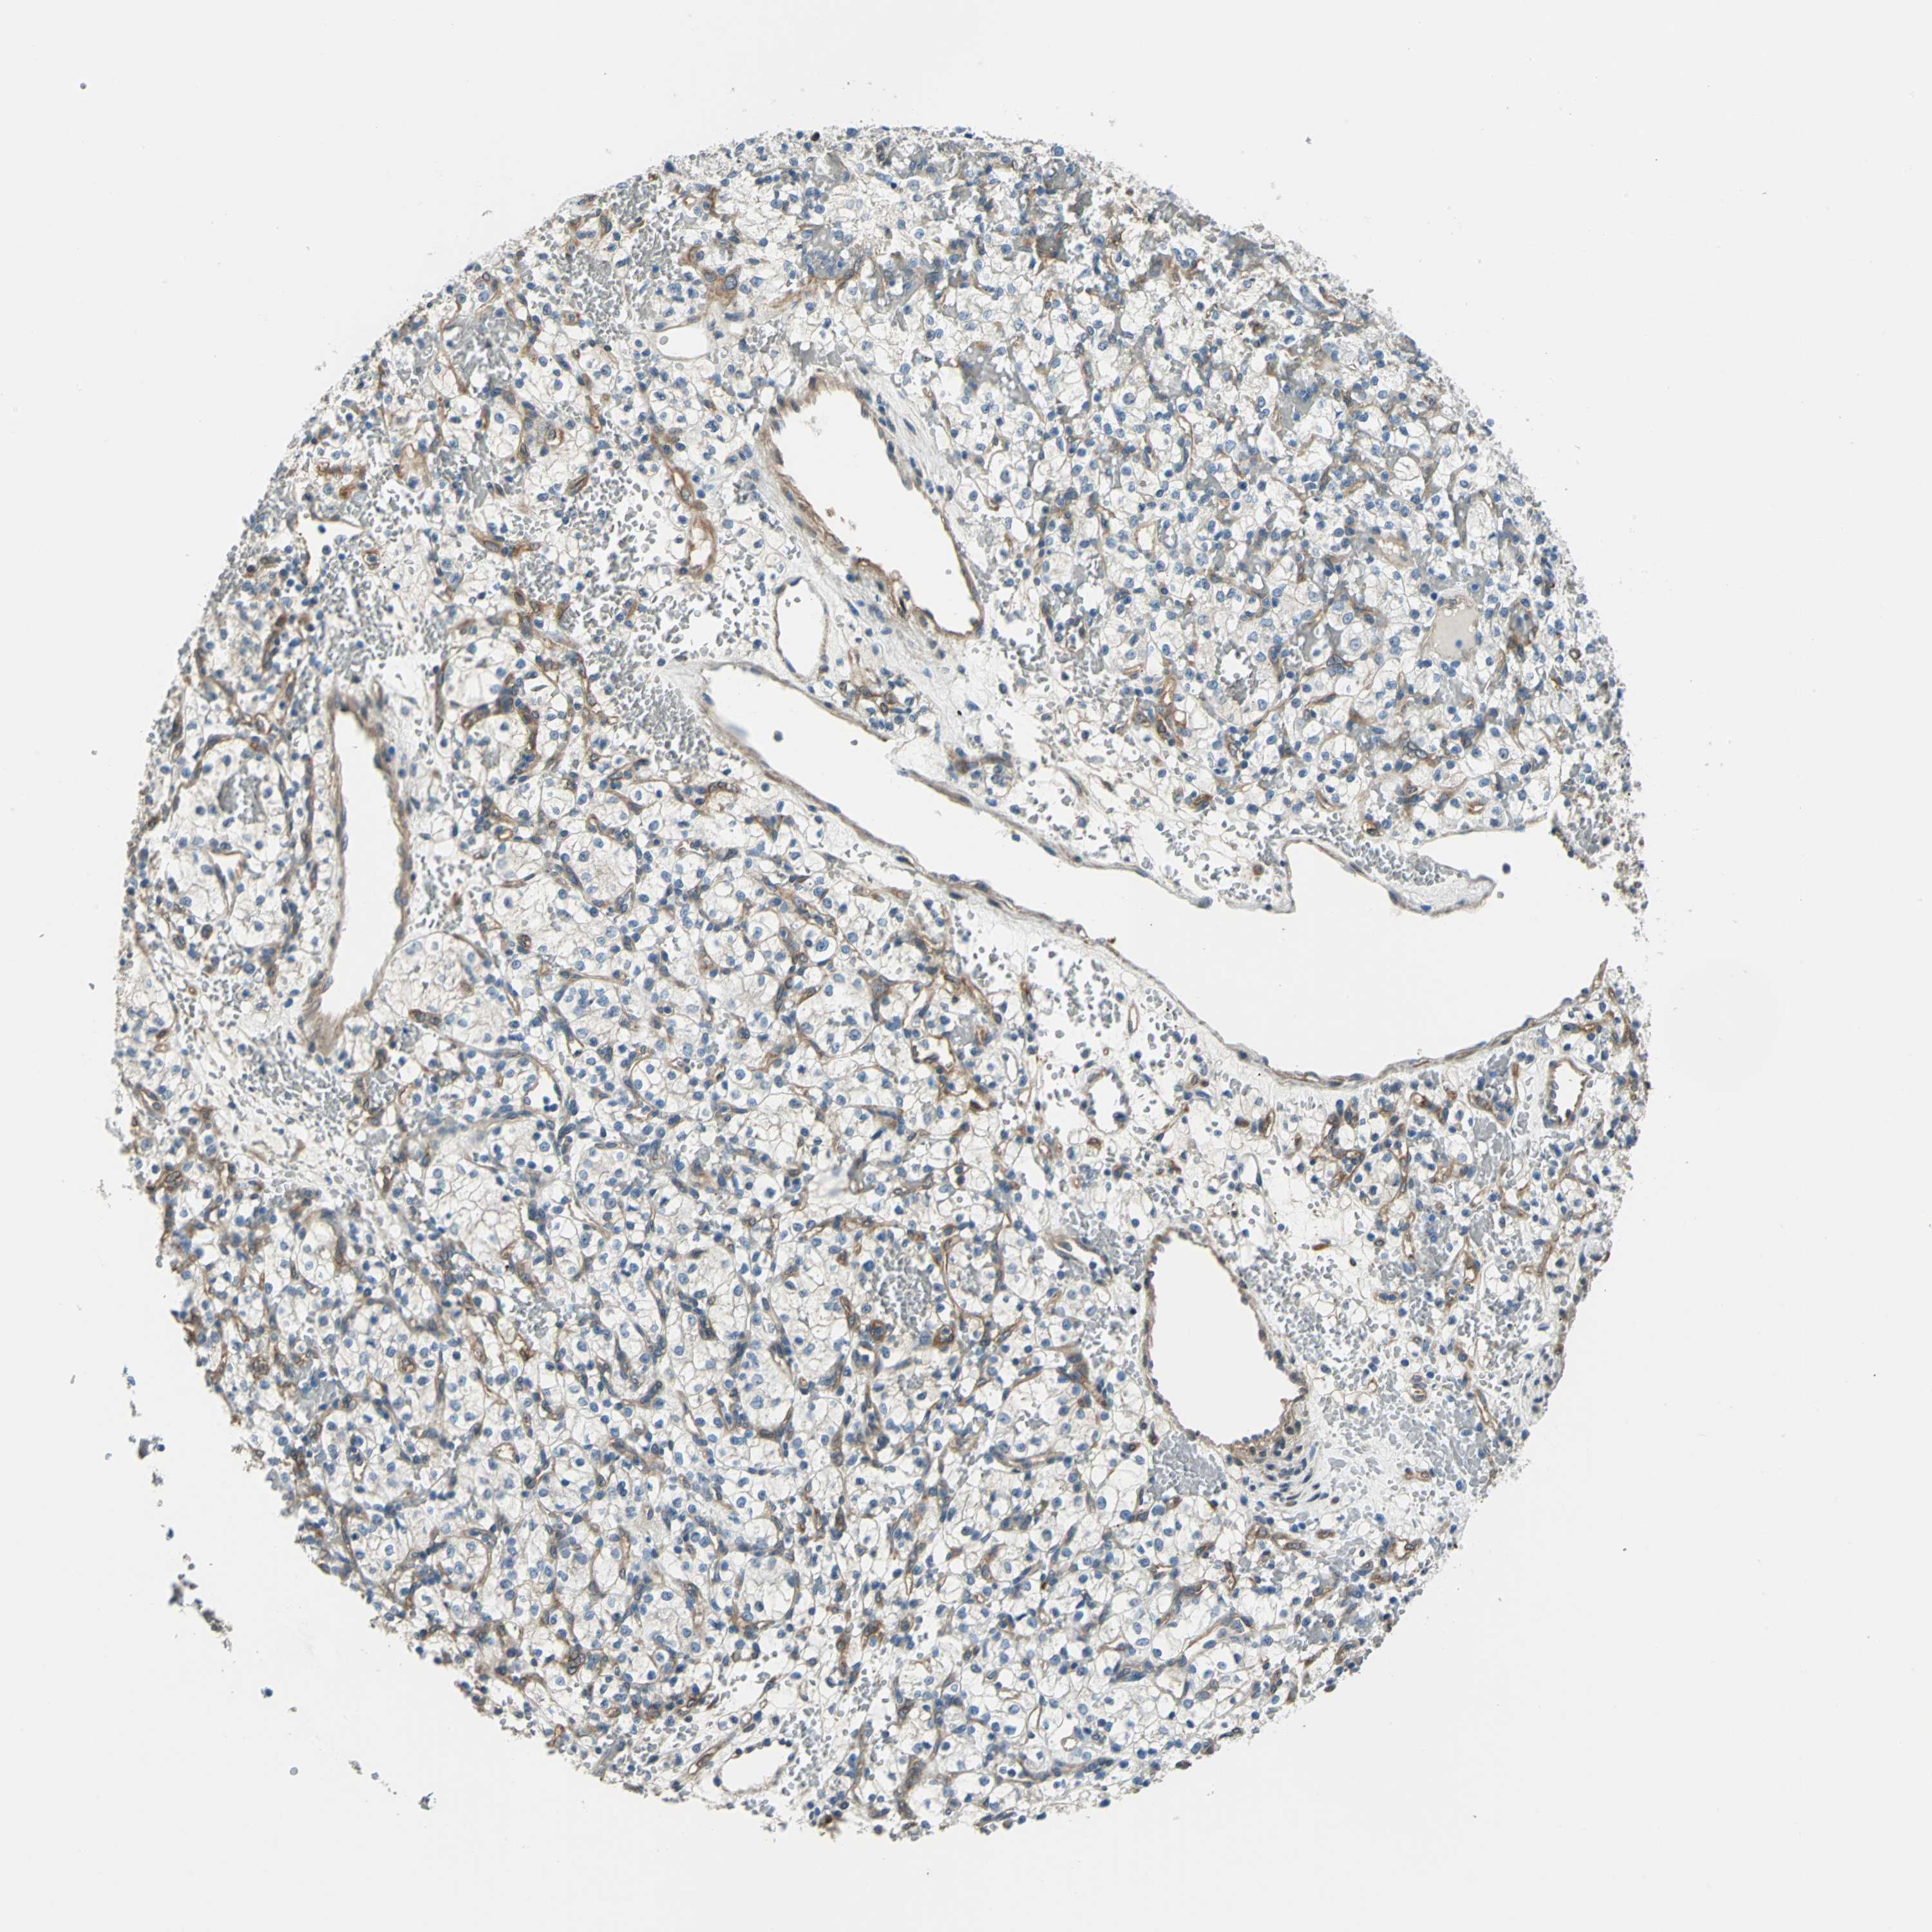

Renal cancer

Kidney renal clear cell carcinoma